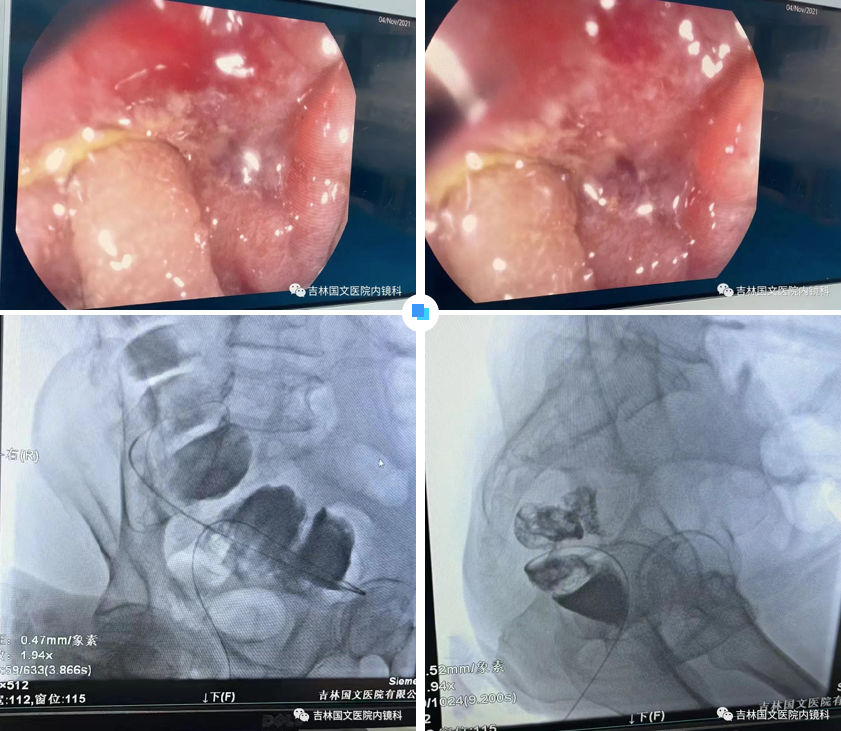

患者為結(jié)腸腫瘤致腸梗阻的病人,通過(guò)放置支架解除患者痛苦。手術(shù)開(kāi)始,先置入導(dǎo)絲與導(dǎo)管,注入造影劑,顯示腸管走形,以確定狹窄段長(zhǎng)度及部位,見(jiàn)乙狀結(jié)腸狹窄,造影劑可通過(guò),但導(dǎo)絲至結(jié)腸狹窄處通過(guò)失敗,候主任決定聯(lián)合內(nèi)鏡,進(jìn)行多學(xué)科合作。

邢主任迅速到達(dá),循腔進(jìn)鏡至乙狀結(jié)腸腫瘤處,見(jiàn)腫瘤環(huán)形生長(zhǎng),腫瘤似豆腐渣樣脆弱又霸道的侵占著本來(lái)就不寬敞的路,中指一樣粗細(xì)的腸鏡是無(wú)法通過(guò)了,只能做一盞指路的明燈,帶領(lǐng)導(dǎo)絲駛?cè)肽康牡兀谛现魅胃挥薪?jīng)驗(yàn)的操作以及候主任隨機(jī)應(yīng)變地配合下,整個(gè)操作行云流水,導(dǎo)絲終于順利通過(guò),送檢病理后,退出腸鏡。

又經(jīng)過(guò)一系列操作,腸道支架順利置入,患者術(shù)后排出大量稀便及氣體,腹脹明顯緩解,解決了患者的生理難題,提高了生活質(zhì)量。